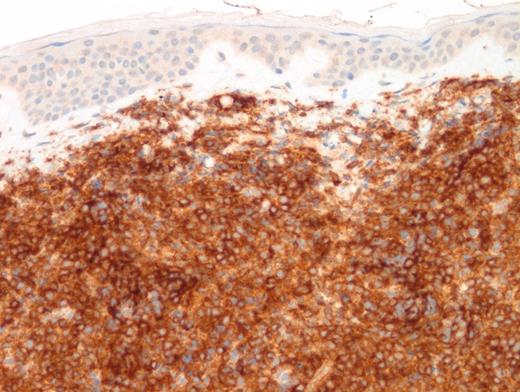

A 15-year-old girl presented with a three-month history of an erythematous rash on the medial side of the left breast. This was initially diagnosed as extramedullary myeloid tumor (EMMT). The patient received standard therapy for acute myeloid leukemia. Although bone marrow and cerebrospinal fluid analysis at the end of therapy showed no evidence of disease, there was cutaneous relapse in three months. An excisional skin biopsy was performed and showed an extensive/malignant appearing infiltrate involving dermis and underlying soft tissue and sparing epidermis and adnexal structures. Images of low- and high-power hematoxylin and eosin (H&E; Figures 1 and 2) as well as CD4 (Figure 3) and CD123 (Figure 4) immunostains are shown. In addition to these markers, a panel of immunostains revealed the dermal infiltrate to be positive for TdT, CD33, CD43, CD45, TCL1, TCF4, and CD68 KP1 (faint, focal).

Low-Power H&E. Extensive, monotonous infiltrate composed of small- to medium-sized cells extending into the dermis. The epidermis is not involved (magnification x400).